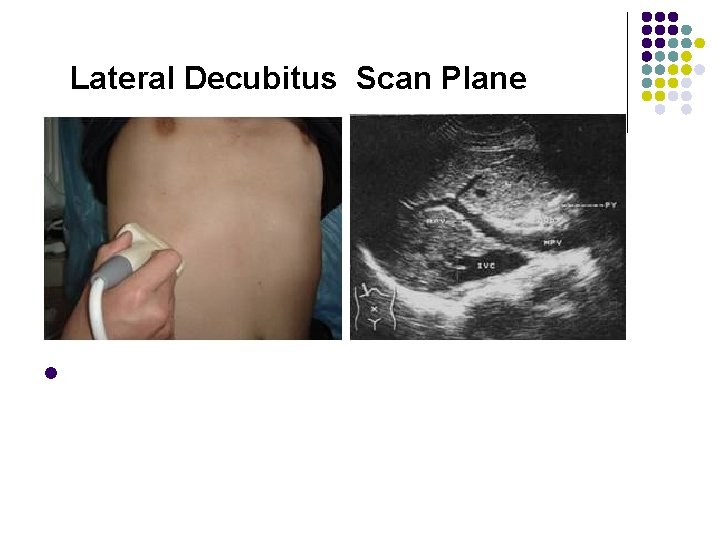

Lateral Decubitus Scan Plane Left Anterior Oblique l The left anterior oblique scan requires that the patient roll slightly to the left. A 45 -degree sponge or pillow may be placed under the right hip to support the patient. This view allows better visualization of the lower right lobe of the liver, usually diaplacing the duodenum and transverse colon to the midline of the abdomen , out of the field of view. Transverse , oblique, or longitudinal scans may be made in this position. l

Lateral Decubitus Scan Plane l